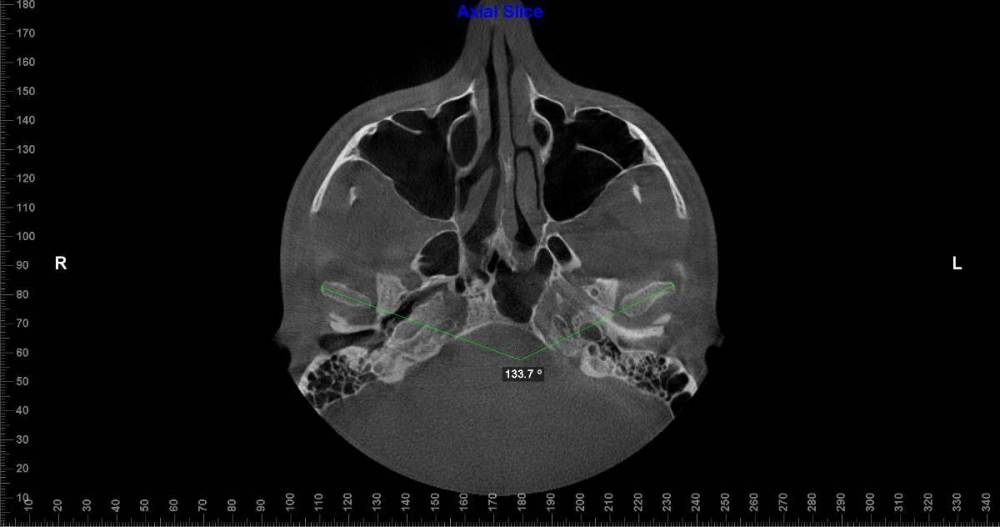

Lotos123 Опубликовано 24 ноября, 2022 Поделиться Опубликовано 24 ноября, 2022 чувствую боль справа и щелчки слева Ссылка на комментарий